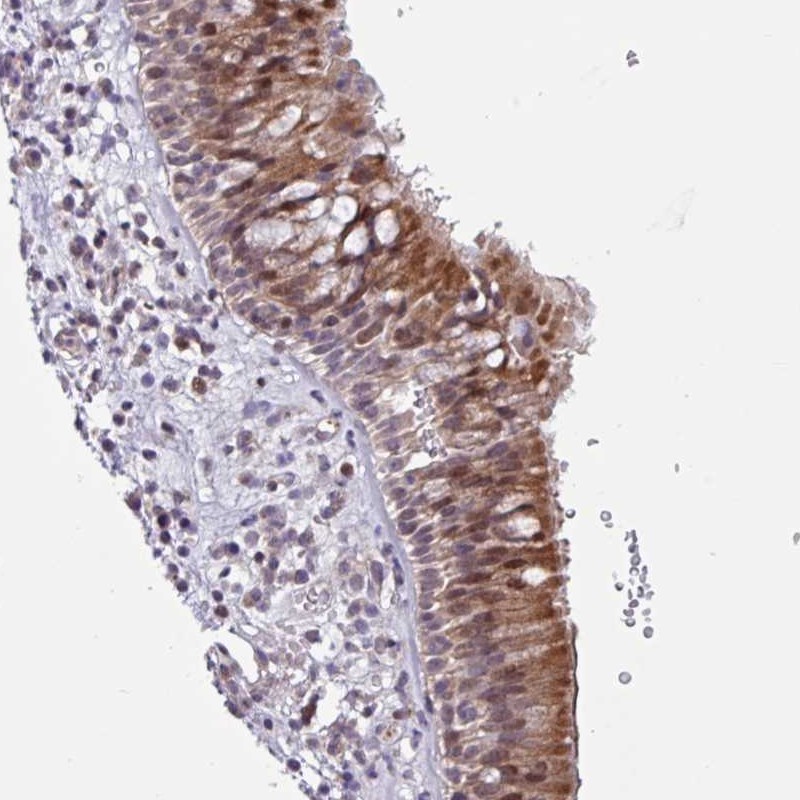

Immunohistochemical staining of human nasopharynx shows strong cytoplasmic and nuclear positivity in respiratory epithelial cells.